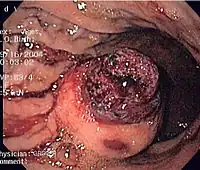

.jpg)

Since GISTs arise from the bowel layer called muscularis propria (which is deeper to the mucosa and submucosa from a luminal perspective), small GIST imaging usually suggest a submucosal process or a mass within the bowel wall. In barium swallow studies, these GISTs most commonly present with smooth borders forming right or obtuse angles with the nearby bowel wall, as seen with any other intramural mass. The mucosal surface is usually intact except for areas of ulceration, which are generally present in 50% of GISTs. Ulcerations fill with barium causing a bull's eye or target lesion appearance. In contrast-enhanced CT, small GISTs are seen as smooth, sharply defined intramural masses with homogeneous attenuation.

Large GISTs

As the tumor grows it may project outside the bowel (exophytic growth) and/or inside the bowel (intraluminal growth), but they most commonly grow exophytically such that the bulk of the tumor projects into the abdominal cavity. If the tumor outstrips its blood supply, it can necrose internally, creating a central fluid-filled cavity with bleeding and cavitations that can eventually ulcerate and communicate into the lumen of the bowel. In that case, barium swallow may show an air, air-fluid levels or oral contrast media accumulation within these areas.[21][25] Mucosal ulcerations may also be present. In contrast-enhanced CT images, large GISTs appear as heterogeneous masses due to areas of living tumor cells surrounding bleeding, necrosis or cysts, which is radiographically seen as a peripheral enhancement pattern with a low attenuation center.[20] In MRI studies, the degree of necrosis and bleeding affects the signal intensity pattern. Areas of bleeding within the tumor will vary its signal intensity depending on how long ago the bleeding occurred. The solid portions of the tumor are typically low signal intensity on T1-weighted images, are high signal intensity on T2-weighted images and enhanced after administration of gadolinium. Signal-intensity voids are present if there is gas within areas of necrotic tumor.[22][26][27]

Features of malignancy

Malignancy is characterized by local invasion and metastases, usually to the liver, omentum and peritoneum. However, cases of metastases to bone, pleura, lungs and retroperitoneum have been seen. In distinction to gastric adenocarcinoma or gastric/small bowel lymphoma, malignant lymphadenopathy (swollen lymph nodes) is uncommon (<10%) and thus imaging usually shows absence of lymph node enlargement.[20] If metastases are not present, other radiologic features suggesting malignancy include: size (>5 cm), heterogeneous enhancement after contrast administration, and ulcerations.[4][20][28] Also, overtly malignant behavior (in distinction to malignant potential of lesser degree) is less commonly seen in gastric tumors, with a ratio of behaviorally benign to overtly malignant of 3-5:1.[4] Even if radiographic malignant features are present, these findings may also represent other tumors and definitive diagnosis must be made immunochemically.